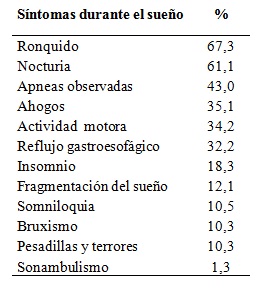

Se presentan los datos recogidos en la historia clínica electrónica desde 2008 a 2014 (n = 447, 291 mujeres y 156 varones). Por claridad expositiva, los síntomas se presentan agrupados en: síntomas durante el sueño, síntomas del despertar y síntomas de la vigilia en la Tabla 2, Tabla 3, y Tabla 4.

Tabla 2: Síntomas durante el sueño

Tabla 2. Frecuencia de pacientes con síntomas relatados durante el sueño por el paciente o su acompañante (n=447).

El ronquido y la somnolencia diurna excesiva persistente fueron los síntomas más frecuentes. La escala de somnolencia de Epworth tuvo un puntaje promedio de 10,4 ± 6,2. Utilizando el límite de corte habitual de 10 puntos, la sensibilidad para predecir más de 5 apneas por hora de sueño fue de 84,3% y la especificidad 16,4%. El 48,6% de los pacientes tuvieron un puntaje igual o mayor a 10, que indica somnolencia moderada a severa. No se encontró correlación entre el puntaje y los índices de severidad de las apneas del sueño: índice de apneas-hipopneas por hora (IAH), Índice de desaturación de oxígeno (IDO) e Índice de despertares (Idesp).

El conocimiento de la presentación clínica del SAHOS ha sido uno de los objetivos principales de nuestro estudio. El abordaje más completo probablemente sea el que utiliza el método estadístico de análisis de conglomerados25. En esa línea de investigación se inscribe la búsqueda de fenotipos fisiopatológicos o conductuales26, que puedan explicar las causas no anatómicas del SAHOS. La descripción de la clínica y de los hallazgos fisiológicos de nuestros pacientes referidos desde 1991 a 1998, fue presentada previamente27. Esta primera revisión de la presentación clínica, probablemente con errores de muestreo, sobresaliencia y ponderación, nos permitió sentar las bases para la recolección prospectiva, con una historia clínica electrónica, de síntomas, signos, repercusiones funcionales, factores de riesgo y factores agravantes. El formulario creado para el ingreso de los datos constituyó, además, un recurso didáctico adicional. Los síntomas principales fueron el ronquido y la somnolencia. Para evaluar a la somnolencia y catalogarla como diurna, excesiva y persistente (característica singulares del SAHOS) se requirió un entrenamiento específico. ya que muchas veces el síntoma es negado, ocultado por vergüenza o simplemente admitido como una característica peculiar innata. La escala de Epworth mostró valores similares a otras series publicadas y resulta inespecífica para su evaluación. EL FOSQ nos ha resultado un instrumento adecuado en el ámbito de la investigación clínica, pero no resulta práctico en la asistencia. Entre los síntomas peculiares, la frecuencia de la nocturia y del reflujo gastroesofágico son destacables, ya que habitualmente se atribuyen a otras patologías28)(29.